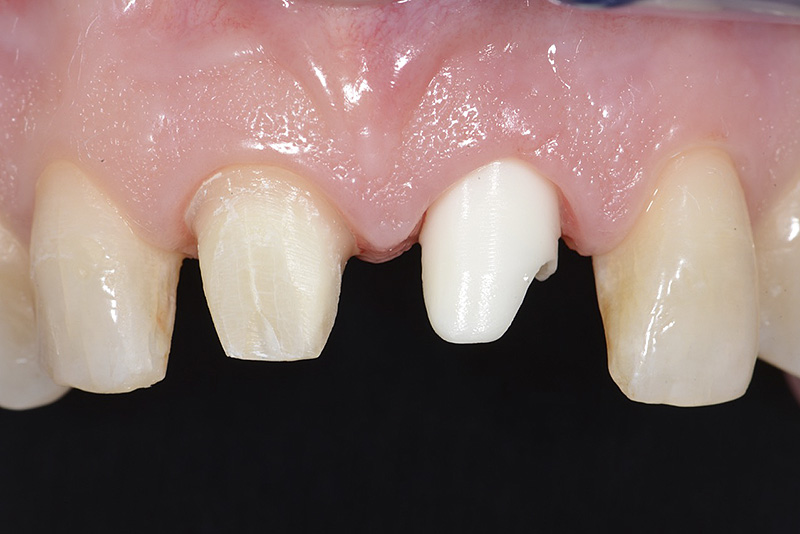

PREMESSA: in seguito all’estrazione dell’incisivo laterale superiore di destra, resasi necessaria per cause batteriche, si decide di affrontare il caso con il posizionamento di un impianto in sostituzione dell’elemento mancante dopo guarigione del sito infetto. Con tecniche rigenerative sia dei tessuti ossei mancanti a causa dell’infezione pregressa, sia dei tessuti gengivali che appaiono inizialmente troppo spostati in alto, si ripristina una corretta morfologia delle parabole (contorni) gengivali e delle papille interdentali (triangoli di gengiva tra due denti vicini).

Vengono utilizzati 2 tipi di provvisori: il primo, cementato ai denti vicini, viene utilizzato dal momento dell’estrazione del dente fino ad impianto osteointegrato (circa 6 mesi); il secondo, avvitato direttamente all’impianto, ha una funzione di prova estetica ma soprattutto di guida per la maturazione dei tessuti gengivali peri-implantari portandoli verso la maturazione completa prima di posizionare la corona finale in disilicato di litio.